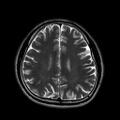

4. TSE(Turbo Spin Echo; 고속스핀에코 기법)

1. 대표사진

2. 동영상-5,6,7

T2 TSE AX(위에서 보면서) T2 TSE COR(앞에서 보면서) T2 TSE SAG(옆에서 보면서)